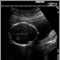

Intrauterine growth restriction (IUGR) may be suspected if the size of the pregnant woman's uterus is small. The condition is usually confirmed by ultrasound.

IUGR increases the risk for intrauterine death. If this condition is suspected, the pregnant woman will be closely monitored with several pregnancy ultrasounds to measure the baby's growth, movements, blood flow, and fluid around the baby. Non-stress testing will also be done. Depending on the results of these tests, delivery may be necessary.